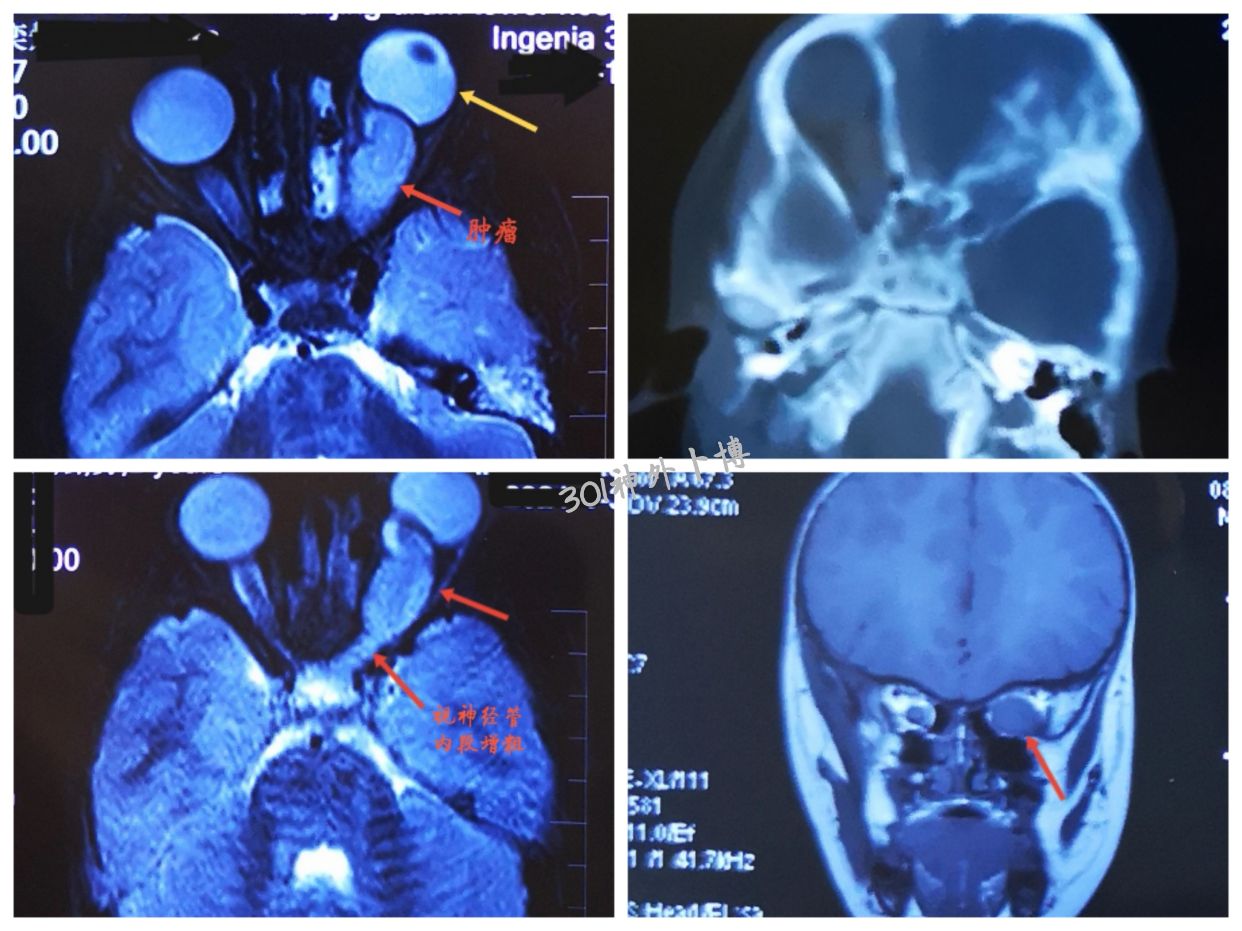

门诊所见。儿童3岁。进行性左眼球突出,左眼失明。考虑视神经胶质瘤。预约增强磁共振。

诊断:左侧视神经胶质瘤。

计划手术:开颅手术,切除肿瘤。保护眼肌及其支配的神经。开放视神经管,切除管内段增粗的视神经。颅内段也要探查(怀疑颅内段也有扩散,等待增强磁共振确认。)。